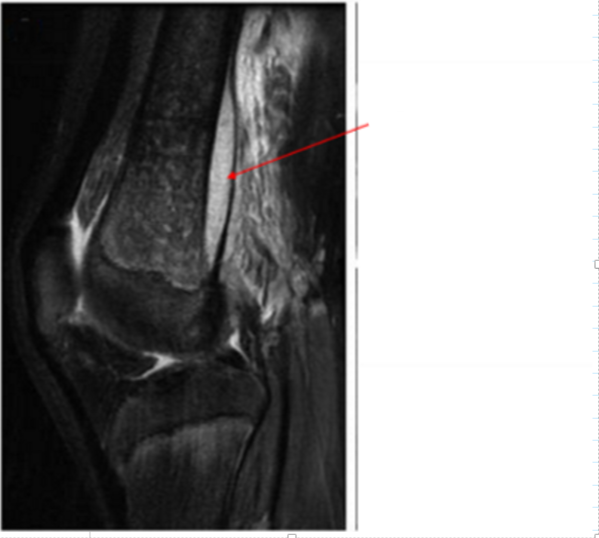

Identify